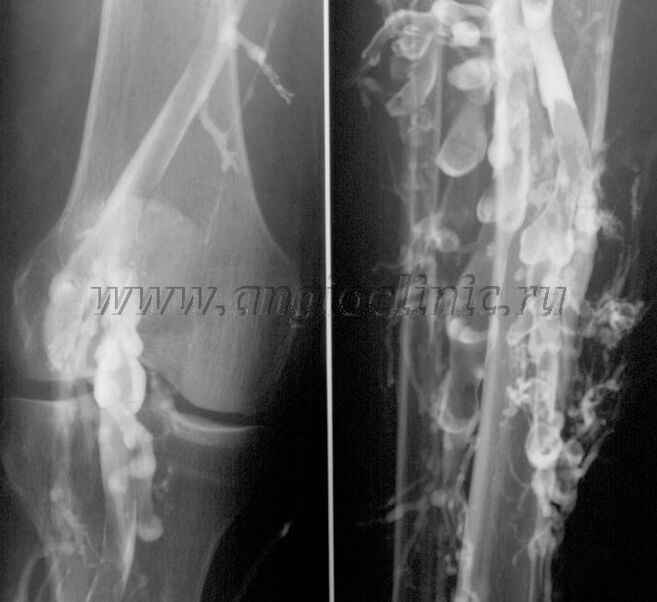

Vélographie contrastée

Habituellement, une échographie suffit pour un diagnostic complet de pathologie veineuse. Cependant, dans certains cas, il est nécessaire d'étudier le lien entre l'état des systèmes veineux profond et superficiel, notamment en cas de rechutes de varices et de varices secondaires.

Examen échographique

Pour résoudre ces problèmes, un examen aux rayons X de contraste est utilisé. Les veines saphènes sont ponctionnées et un produit de contraste est administré. Le mouvement du produit de contraste est observé sur le moniteur de l'appareil à rayons X et tous les tests et projections nécessaires sont effectués. La phlébographie n'est actuellement utilisée que très rarement pour les varices.